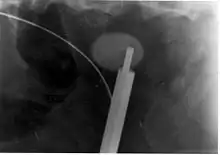

- Nefrolitotomía percutánea.

- Es una técnica en la cual se hace una pequeña incisión en el flanco del lado afectado y se utiliza un transductor de ultrasonido o láser de holmio para desintegrar el cálculo (ureteroscopia con desintegración del cálculo por medio de láser holmio)